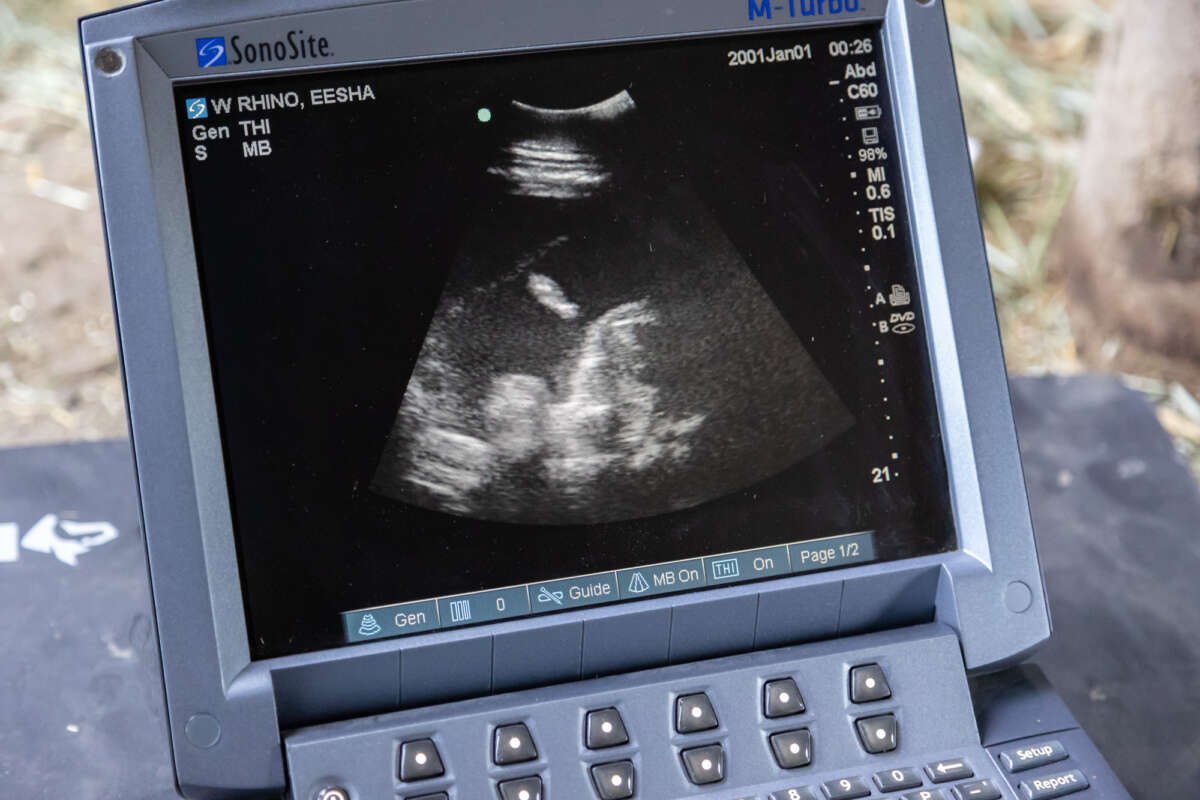

Ultrasound looking for baby rhino by Mark Pressler

Ongava came to Safari West as a recommended breeding match from the Association of Zoos and Aquariums’ White Rhino Species Survival Plan, or SSP, ensuring a healthy genetic pairing. When Eesha and Ongava were introduced, the pair exhibited the assertive behaviors normally seen in rhino courtship, as well as a few attempts at breeding. Throughout 2022 we saw positive signs of pregnancy. Blood draws revealed continuously elevated levels of the hormone progesterone, and regular transabdominal ultrasounds displayed calf movement! Safari West initiated a research project involving weekly thermal imaging of Eesha. Results are being compared to the established methods of determining and monitoring pregnancy, to see if thermography is a viable alternative way to monitor pregnancy in rhinos. Stay tuned for a more in-depth look at the research we are conducting to benefit rhinos in the wild and under human care!

Dr. Cehrs doing ultrasound on Eesha by Mark Pressler